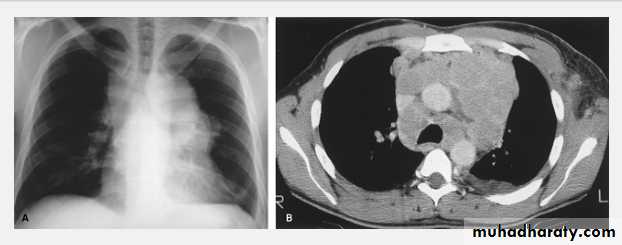

Massive pleural effusion with mediastinal shift to the left.

(A) Chest radiograph

(B) CT coronal reconstruction. A massive effusion displaces the mediastinum to the left. CT shows the important pleural effusion together with the enhanced atelectatic left lung.

Note also the depression of the right hemidiaphragm (arrows).